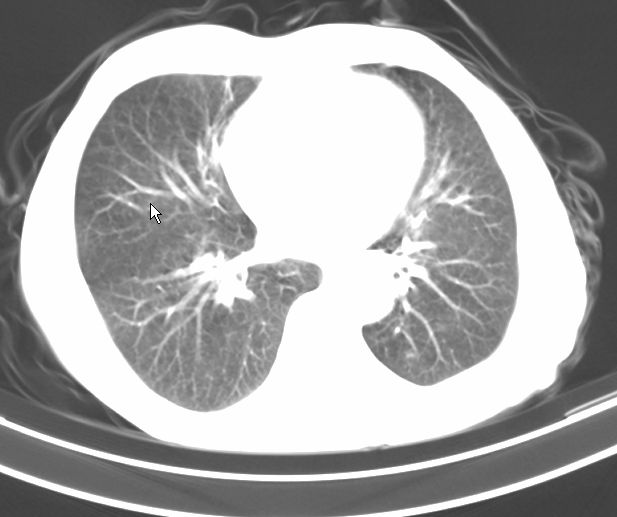

请大家看看是什么性质的。炎性病变首先考虑哪一种炎症。

支持右肺上叶前段\\下叶内基底段感染,建议抗炎治疗后复查,除外结核.

支持右肺上叶前段\\下叶上段感染,建议抗炎治疗后复查,除外结核.

支持右肺上叶前段、下叶内基底段感染,建议抗炎治疗后复查,除外结核.

右肺上叶前段及下叶内基底段感染性病变;建议抗炎治疗后复查。

楼主说是炎症,凭啥?典型的周围型肺癌(腺癌可能性大),肝内可能已有转移,强化看看吧。